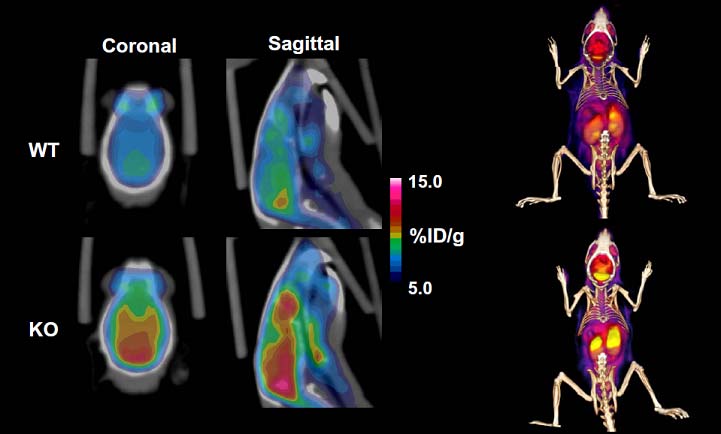

These PET/CT images demonstrate that a 64Cu-labeled GLP-1 analog specifically target pancreatic beta cells in a mouse.

Mice receiving the radiotracer showed a significantly elevated signal in the pancreas region as compared to mice co-injected

with unlabeled exendin-4 (competitive binding) or in STZ-treated mice lacking beta cells. The imaging result was further

confirmed by ex vivo imaging of the organs of interest excised from the mice and immunohistochemical staining of corresponding tissue slices.

Quantitative dynamic PET images of FDG (18F-deoxyglucose) uptake into the brains of WT versus p35 KO mice demonstrate 50 % greater

uptake of glucose in the KO animals. This indicates that the absence of p35 results in an increase in glucose metabolism in brain.

This study also demonstrates that small animal PET/CT is able to distinguish compartments within the brain and differences in the rate of

glucose metabolism in those compartments may aid in diagnosis of hyperactivity disorders in patients.